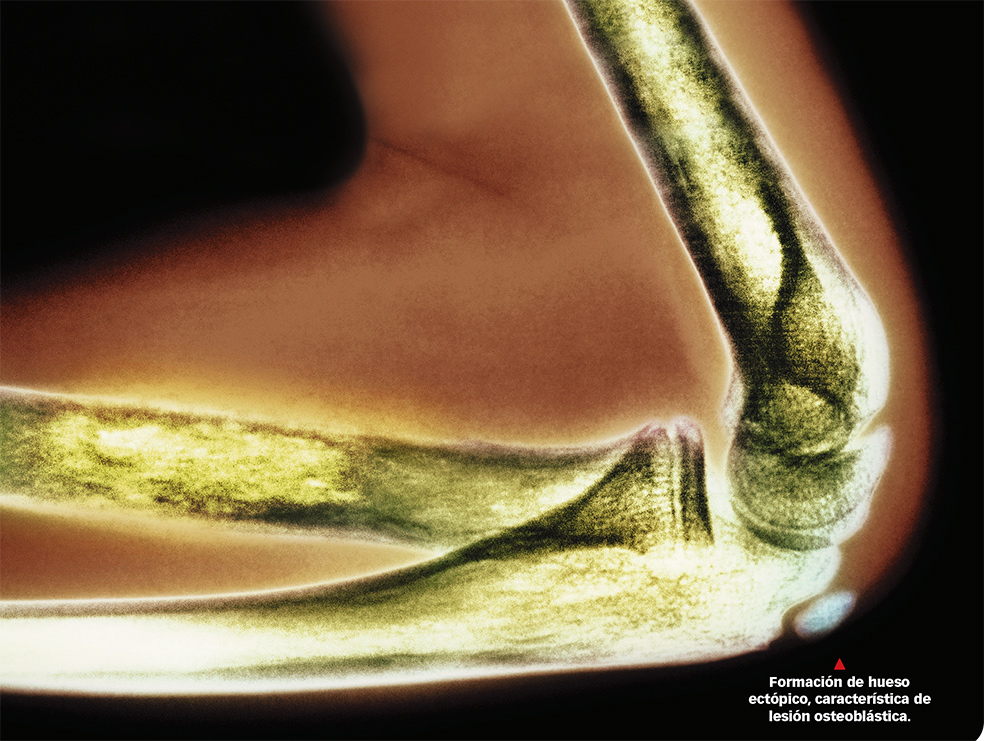

¿Qué es? La tumoración de este órgano es infrecuente: 1 de cada 500 cánceres son óseos. Así y todo, es habitual como síntoma de la metástasis de otros cánceres, sobre todo del mieloma múltiple y del de próstata, mama y pulmón.

¿Cómo ocurre? Las metástasis óseas reproducen el llamado ‘remodelado óseo’, pero de modo pernicioso, no creando hueso, como en ese ciclo, sino destruyéndolo. Suele tener mal pronóstico. En cambio, el tumor de hueso primario (iniciado en el propio hueso, no por metástasis de otro tumor) suele tener buen pronóstico si no ha metastatizado.

¿Hay nuevas terapias? El tratamiento de las metástasis óseas forma parte del específico de cada cáncer, aunque ya hay fármacos específicos, como los bifosfonatos, utilizados conjuntamente con otros para tratar la hipercalcemia tumoral.